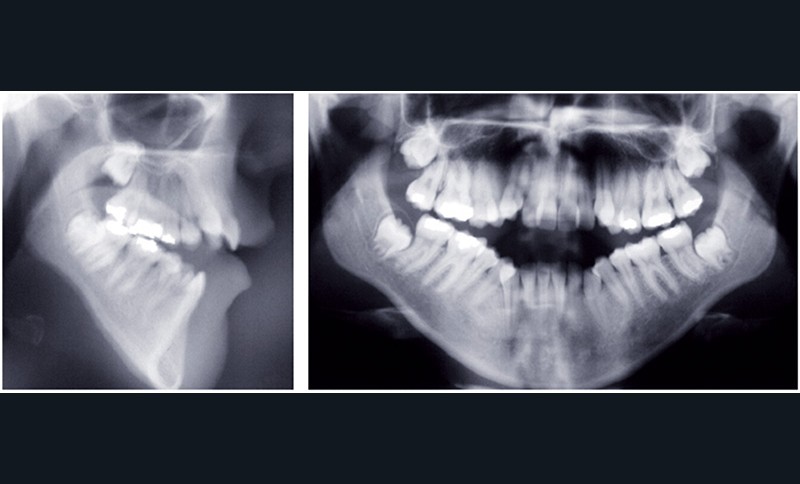

Au niveau squelettique, elle présente une classe I associée à une endognathie maxillaire et une hyperdivergence mandibulaire majeure liée à un excès de croissance alvéolaire verticale postérieure maxillaire et une inclinaison mandibulaire très marquée (fig. 1 et 3).

Sur le plan occlusal et dentaire, on observe une classe I molaire, une occlusion transversale en bout à bout à droite et inversée à gauche et une béance antérieure sévère s’étendant jusqu’aux molaires. Un encombrement est présent aux deux arcades avec des dystopies canines importantes (fig. 2).

• une préparation orthodontique préchirurgicale avec extraction des quatre premières prémolaires qui a assuré la correction de l’encombrement, la décompensation de la malocclusion et l’harmonisation des formes d’arcades (fig. 4 et 5),